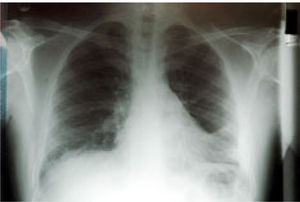

He had positive double stranded anti-DNA (ds-DNA) at 39 RU/mL (normal range: 0-20), positive anti-smooth muscle antibody (ASMA) with titre 1:160 and positive anti-nuclear antibody (ANA) with titre 1:40. His anti-mitochondrial antibodies (AMA) were negative and his Im-munoglobulin G (IgG) was raised only marginally at 17.2 (normal range: 6.0-15.0). A liver biopsy was obtained & showed changes of interface hepatitis with lobular necrosis, cholestasis and pericellular fibrosis while, in the portal tract edges non-caseating granulomas and lymphoid aggregates were present. Due to complaints of chest pain - on a follow-up examination-, a chest radiograph was requested (Figure 1) This x-ray was repeated one month later (Figure 2), while his CT scan findings are shown in figure 3.

The diagnosis of autoimmune hepatitis complicated by lymphocytic interstitial pneumonitis was made and after a detailed but negative septic screen the patient was started on prednisone and later on azathioprine and showed remarkable improvement of both the liver biochemistry and long-lasting resolution of his radiographic findings.

LIP is more common in women (average age 55 years) and it has been associated with autoimmune diseases, pulmonary infections, immunodeficiency, serum dysproteinaemias and drug reactions and graft vs host disease (GVHD). Symptoms mostly consist of chronic cough, dyspnoea, weight loss, fatigue and rarely fever while, haemoptysis or chest pain can occur. Few patients (< 4%) are asymptomatic on presentation. Chest x-ray findings include reticular or reticulonodular opacities and to a lesser extend hilar lymphadenopathy, pleural effusions and honeycomb appearance (from extended fibrosis).4,6 High resolution Ctscan images typically show subpleural fibrosis (predominately in basal areas), ground-glass attenuation, traction bronchiectasis and pulmonary parenchymal cysts.3,5